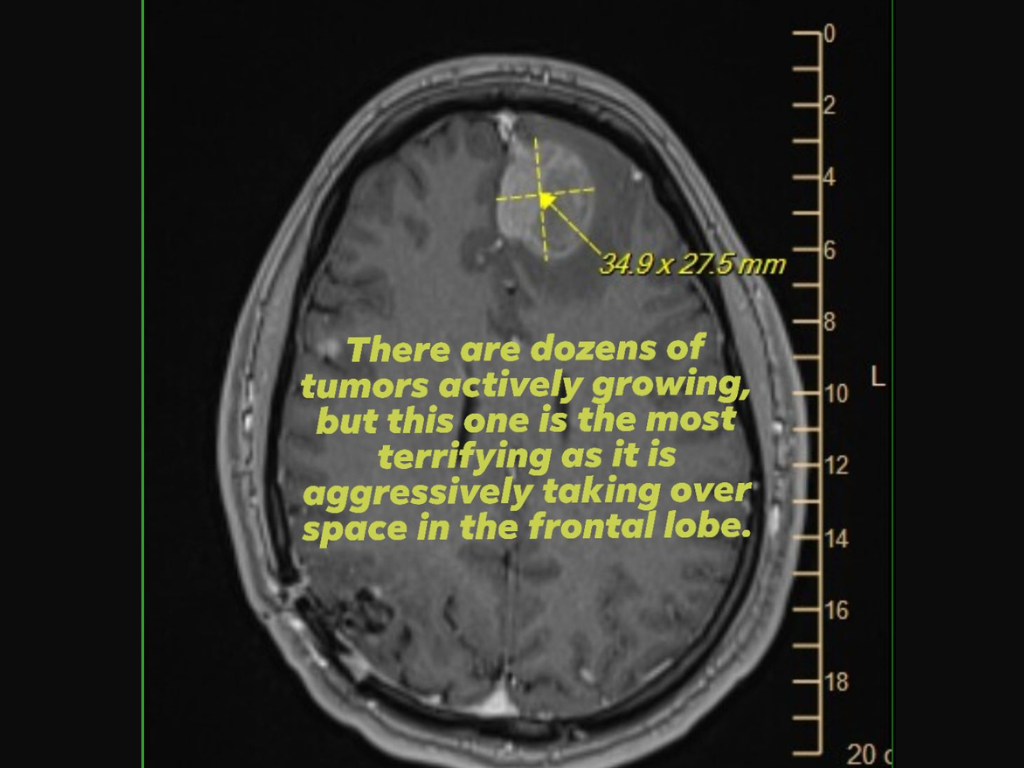

为了证明这一点,她还附上了一张脑部扫描(核磁共振成像)图片,显示额叶患有侵袭性肿瘤,同时恳求 Epic Games 的高管们给予支持或帮助,因为裁员的关键决定是由他们做出的。